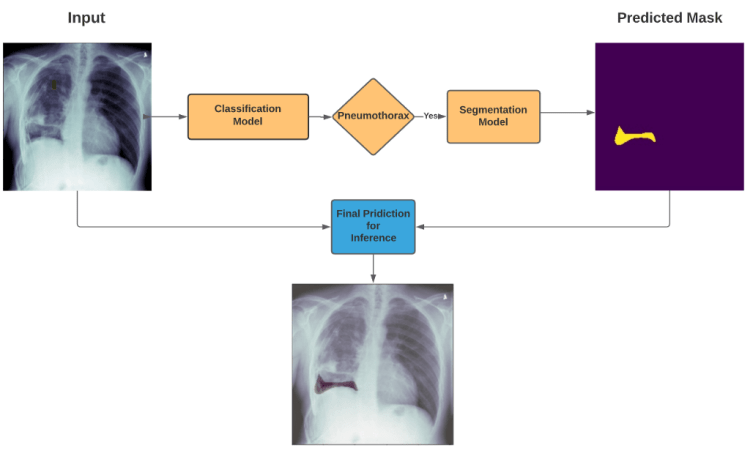

we will try to solve this problem in two Phase:

1 Pneumothorax Classification:

2 Pneumothorax Segmentation

So, in first phase we will develope a classification model to classify Pneumothorax and in Second Phase we will build a model for segmentaiton task on given image

How prediction pipeline will work?

if Classification model detects the Pneumothorax in input X-Ray image then our Prediction Pipeline will pass that X-Ray image to Segmentation Model to segment the Pneumothorax in That X-ray image so that Radiology Expert can easily Analyze and Diagnose this Problem

7. Inference Pipeline:-

So as I mentioned in earlier in Inference pipeline’s Diagram ,

we will only predict the segmentation mask for input Chest X-Ray image if our Classifier will detects any Pneumothorax in that X-ray Image, otherwise there is no mean to predict the segmentation mask for that